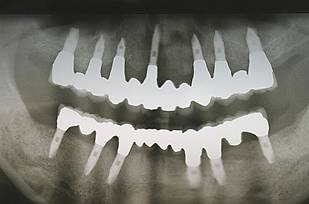

術前パノラマレントゲン写真。根の周りが黒くなり、骨がなくなっていることがわかります